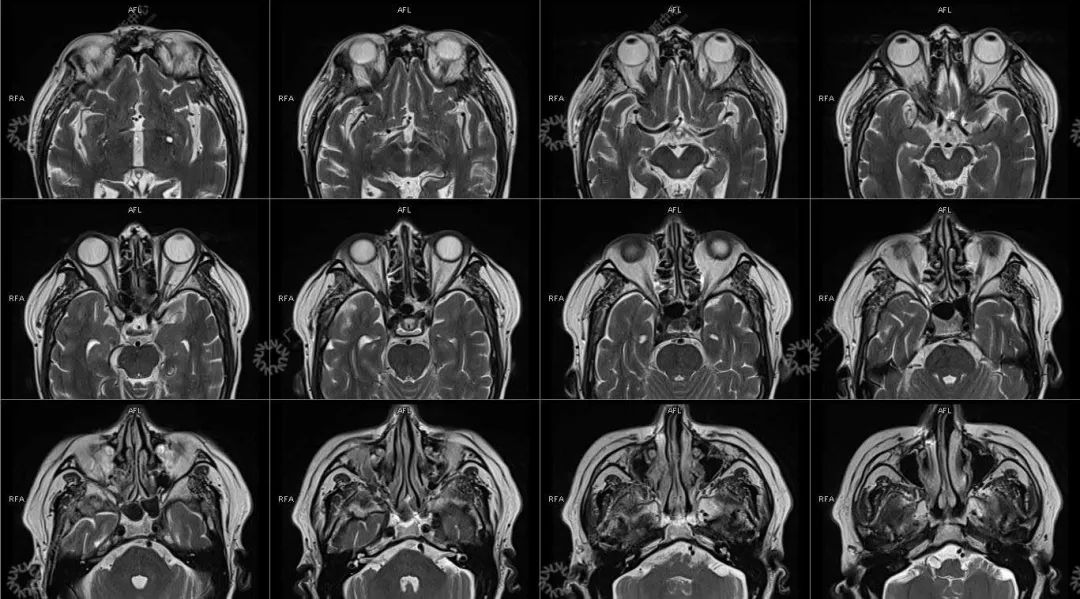

主诉:视力下降 2 年

现病史:双眼部隐痛、流泪,视力下降 2 年

结合影像及实验室检查,临床最终考虑 IgG4 相关性疾病。

●受累器官常表现为弥漫性或局限性肿大或形成肿块, 易误诊为恶性肿瘤